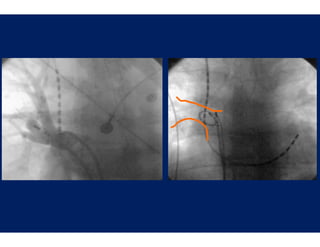

Wide Area Circum

mferential Ablation

Oral et al.: Circulat

tion 2003;108;2355-60

Procedural Success

P    d al S

Elimination of Pulmo

onary Vein Potentials

During A

Ablation

Wide Area Circum mferential Ablation Oral et al.: Circulat tion 2003;108;2355-60

• 71.

Procedural Success P d al S Elimination of Pulmo onary Vein Potentials During A Ablation